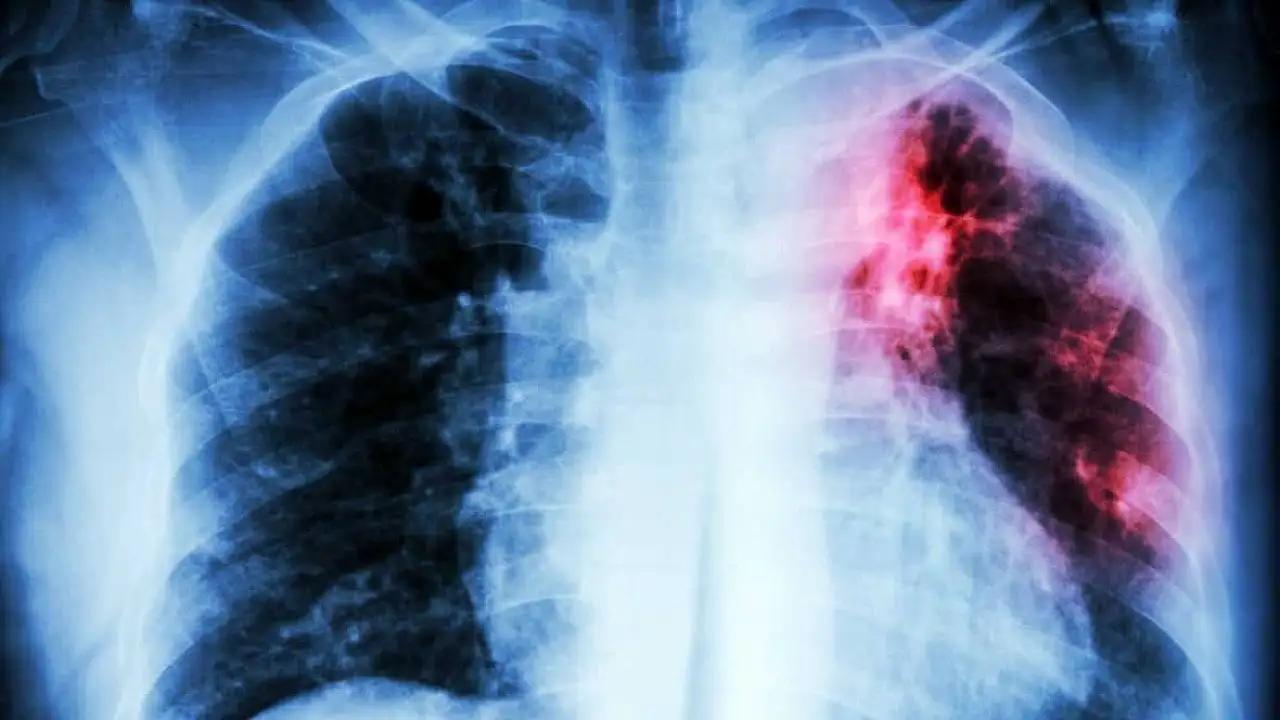

Tanıda yakınmalar ve akciğer filmi önemli

Tüberküloz tanısının balgamda verem mikrobunun gösterilmesi ile konulduğunu vurgulayan Uzm. Dr. Saliha Ercan Bütün, şu bilgileri paylaştı:

“Hastanın yakınmaları ve akciğer film bulguları tüberkülozdan şüphelenmeyi sağlar. Hastadan alınan balgam ve diğer materyallerde tüberküloz basilinin görülmesi ya da ekilen kültürde basil üretilmesiyle tanı kesinleşir. Yapılan PPD testi kişinin daha önce tüberküloz basilliyle karşılaşıp karşılaşmadığını gösterir. Kişinin PPD sinin (+) olması verem hastası olduğunu göstermez. Tüberküloz tedavisi için günümüzde çok güçlü ilaçlar bulunmaktadır ve başlangıçta 4 ilaç kullanılmalıdır. Yapılan balgam sonuçlarına göre tedavi en az 6 aydır.”